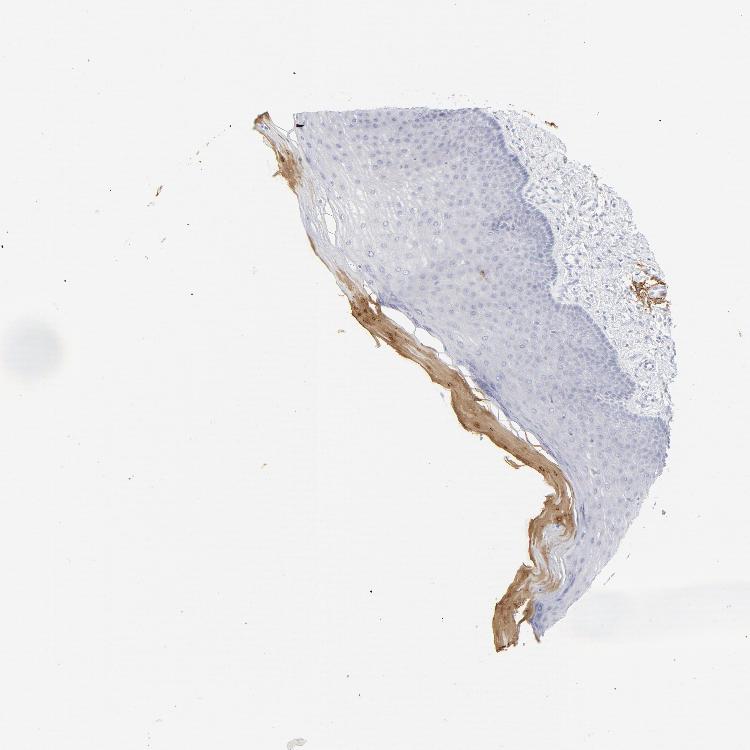

CERVIX - Antibody stainingi

Antibody staining in the annotated cell types in the current human tissue is reported as not detected, low, medium, or high, based on conventional immunohistochemistry profiling in selected tissues. This score is based on the combination of the staining intensity and fraction of stained cells.

Each image is clickable and will lead to virtual microscopy that enables deeper exploration of all samples and also displays staining intensity scores, fraction scores and subcellular localization as well as patient and tissue information for each sample.

Antibody CAB003796

Glandular cells Not detected

Squamous epithelial cells Low